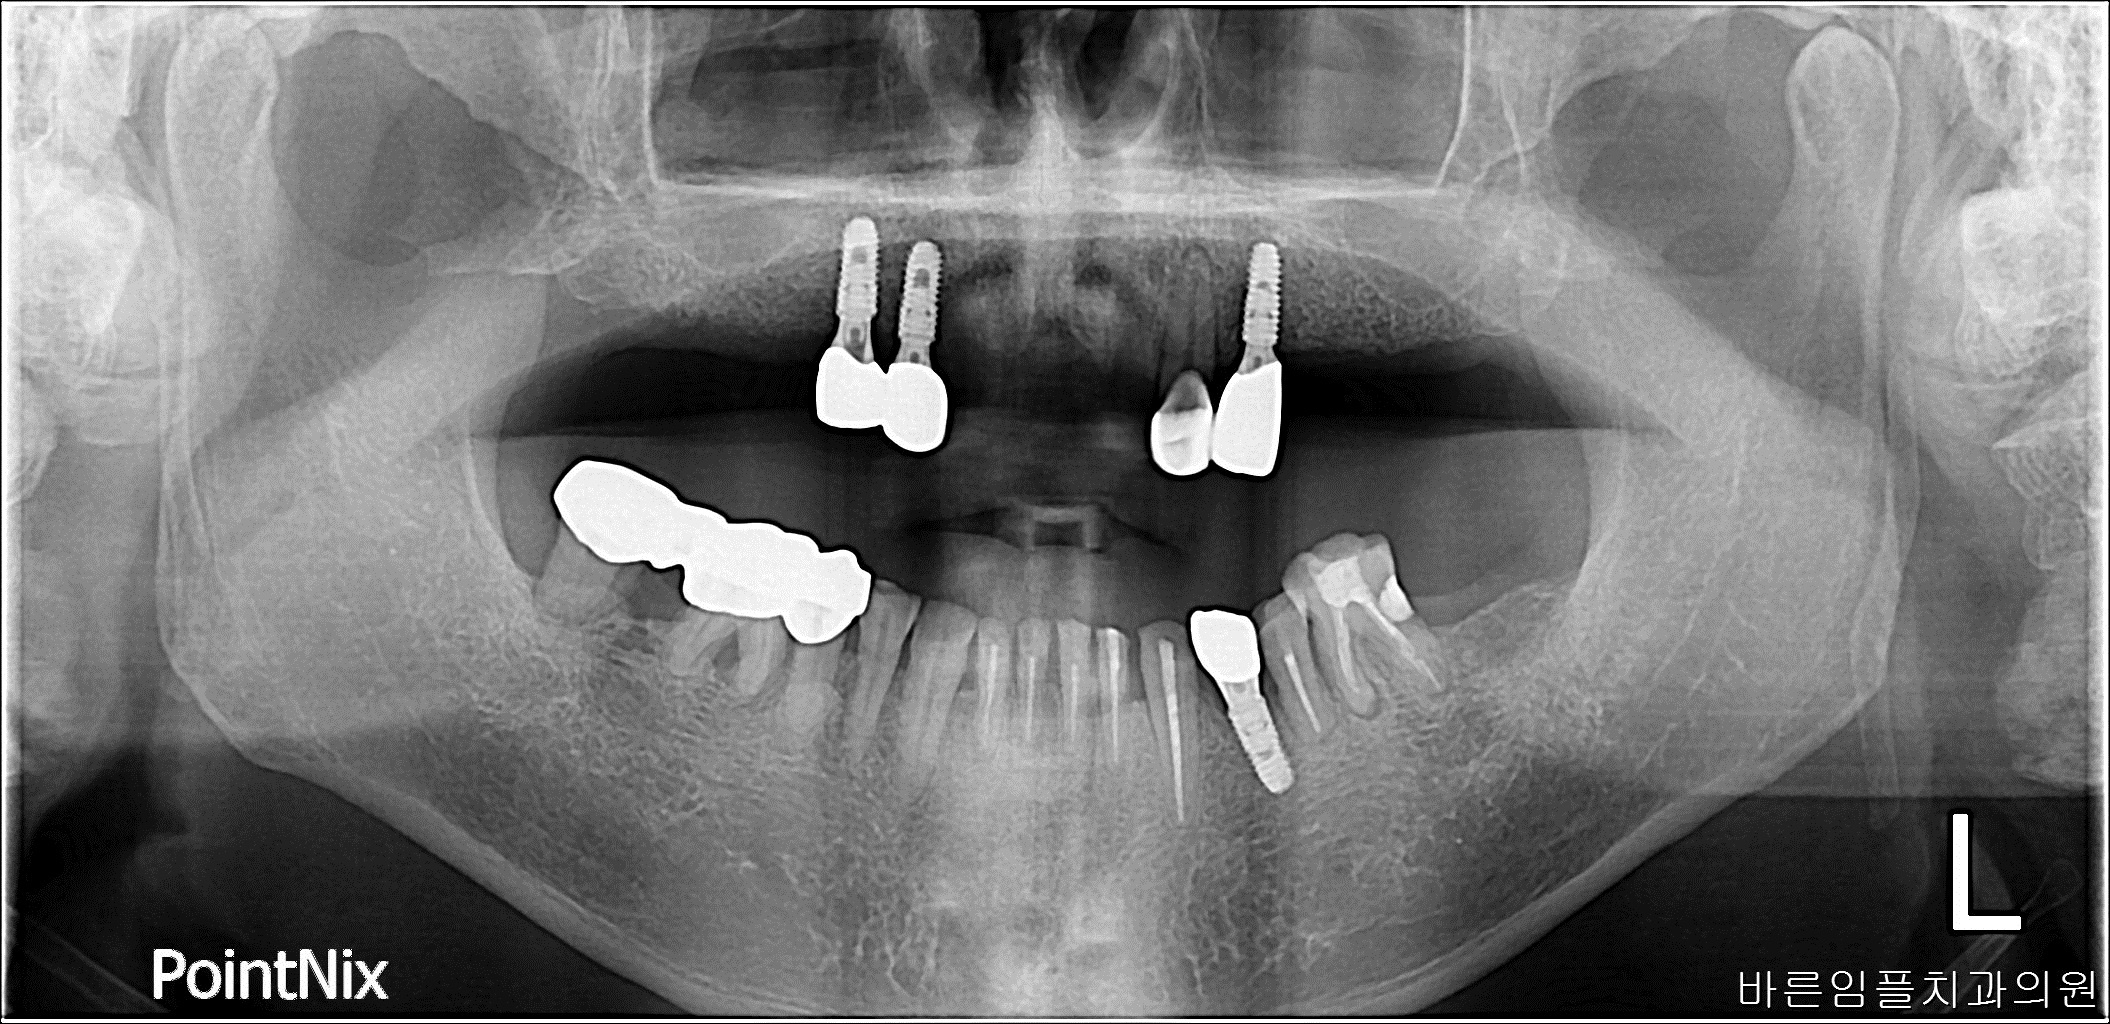

김ㅇㅇ / 임플란트 페이지 정보 작성일 23-10-27 16:55 2023-04-23 김ㅇㅇ Before 2023-08-21 김ㅇㅇ After 김ㅇㅇ / 임플란트 목록 이전글김ㅇㅇ / 수면임플란트